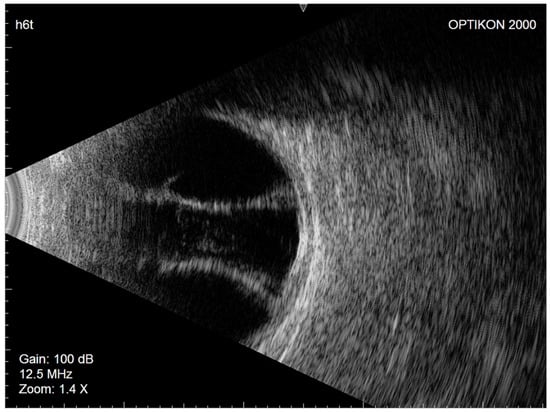

Considering the patient’s demographic and ocular characteristics and ideal IOP target, XEN45 implantation was selected as the most suitable glaucoma filtering surgery. In July 2020, XEN45 implantation with a subconjunctival injection of mitomycin C (0.2 mg/mL) was performed in the right eye. No intraoperative complications occurred. The day after surgery, the IOP was 10 mmHg, the filtration bleb appearance was excessively diffuse, and the anterior chamber was flat. Nasal and temporal CDs were visible on fundus examination, and their serous nature was confirmed by eco-B scan (Figure 2).

In March 2021, the left eye (similar to the fellow eye) underwent an uneventful ab interno XEN45 device implantation. The day after surgery, the IOP was 7 mmHg, the bleb morphology was diffuse, and the anterior chamber was deep. Seven days later, similar to the right eye, nasal and temporal CDs were observed on fundus examination and confirmed as serous CDs on eco-B scan (Figure 3).

Figure 2. Right eye Eco-B scan showing serous choroidal detachment.

Figure 3. Left eye Eco-B scan showing serous choroidal detachment.